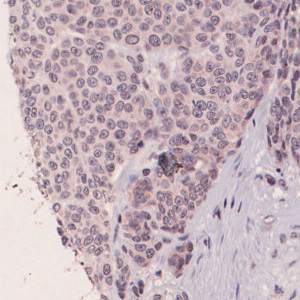

Figure 1

Nuclei surrounded by iNOS intermediate and low staining.